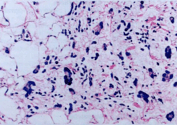

图片显示的脂肪组织肿瘤是()

A、多形性脂肪肉瘤

B、梭形细胞脂肪瘤

C、脂肪母细胞瘤

D、多形性脂肪瘤

E、圆形细胞脂肪肉瘤